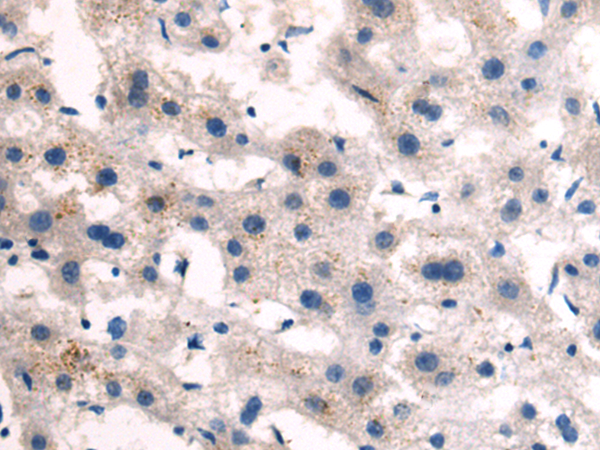

分类: 科研抗体货号: P11248别名: TKT; MIG20a; NTRKR3; TYRO10应用: IHC反应种属: Human, Mouse